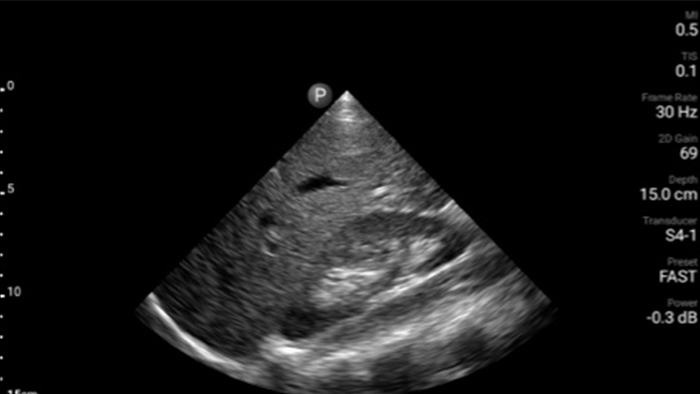

Exceptional ultrasound imaging

Lumify handheld ultrasound offers images that enhance diagnostic confidence.

See more when it counts

Lumify can help you make real-time decisions with more confidence, from assessment to recovery. Reveal the subtle details of an image, uncover enriched tissue definition with multiple angles and much more.